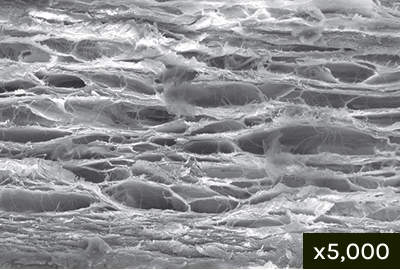

Cross Section

Multi-layer Heterostructure